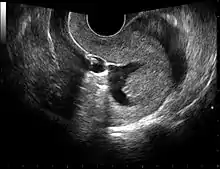

The examination can be performed by transabdominal ultrasonography, generally with a full bladder which acts as an acoustic window to achieve better visualization of pelvis organs, or by transvaginal ultrasonography with a specifically designed vaginal transducer. Transvaginal imaging utilizes a higher frequency imaging, which gives better resolution of the ovaries, uterus and endometrium (the fallopian tubes are generally not seen unless distended), but is limited to depth of image penetration, whereas larger lesions reaching into the abdomen are better seen transabdominally. Having a full bladder for the transabdominal portion of the exam is helpful because sound travels through fluid with less attenuation to better visualize the uterus and ovaries which lies posteriorly to the bladder. The procedure is by definition invasive when performed transvaginally. Scans are performed by health care professionals called sonographers, or gynecologists trained in ultrasound.

Sonohysterography

Sonohysterography is a specialized procedure by which fluid, usually sterile saline (then called saline infusion sonography or SIS), is instilled into the uterine cavity, and gynecologic sonography performed at the same time. A review in 2015 came to the conclusion that SIS is highly sensitive in the detection of intrauterine abnormalities in subfertile women, comparable to hysteroscopy. SIS is highly sensitive and specific test in the diagnosis of uterine polyps, submucous uterine fibroids, uterine anomalies and intrauterine adhesions (as part of Asherman's syndrome), and can be used as a screening tool for subfertile women prior to IVF treatment.[4]